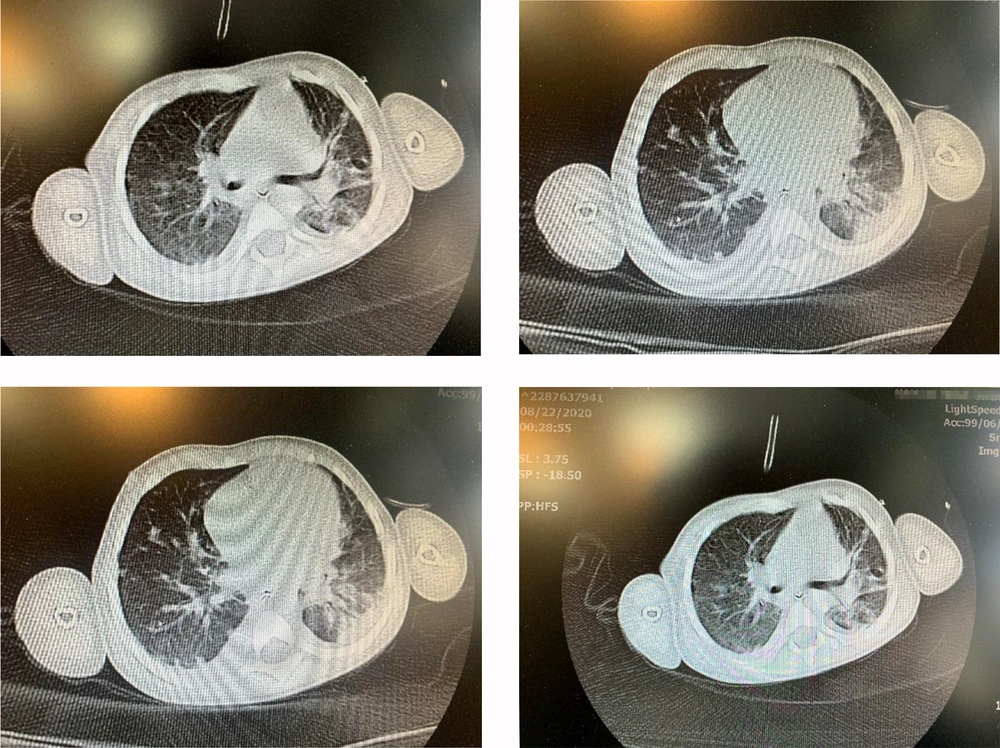

Due to the COVID-19 outbreak, the PCR of COVID-19 was done on samples of the pharynx and nasopharynx of the patient, which turned positive. Spiral HRCT of lungs showed patchy ground-glass and patchy consolidations in the upper and lower lobes of both lungs, which was in favor of COVID-19 infection (Figure 2). The patient had undergone echocardiography, which revealed a mildly dilated left ventricle and good biventricular function. On the second day after admission, a peripheral blood smear was taken, which showed leukopenia (lymphocyte dominant), hypochromic RBCs, moderate Burr cell count, a few acanthocytes, and severe thrombocytopenia as well as a few large platelets. Based on the pediatric hematologist and pediatric ICU specialists’ recommendations, vasopressors and management of PF were started promptly. The patient was transferred to the pediatric ICU after a few hours.